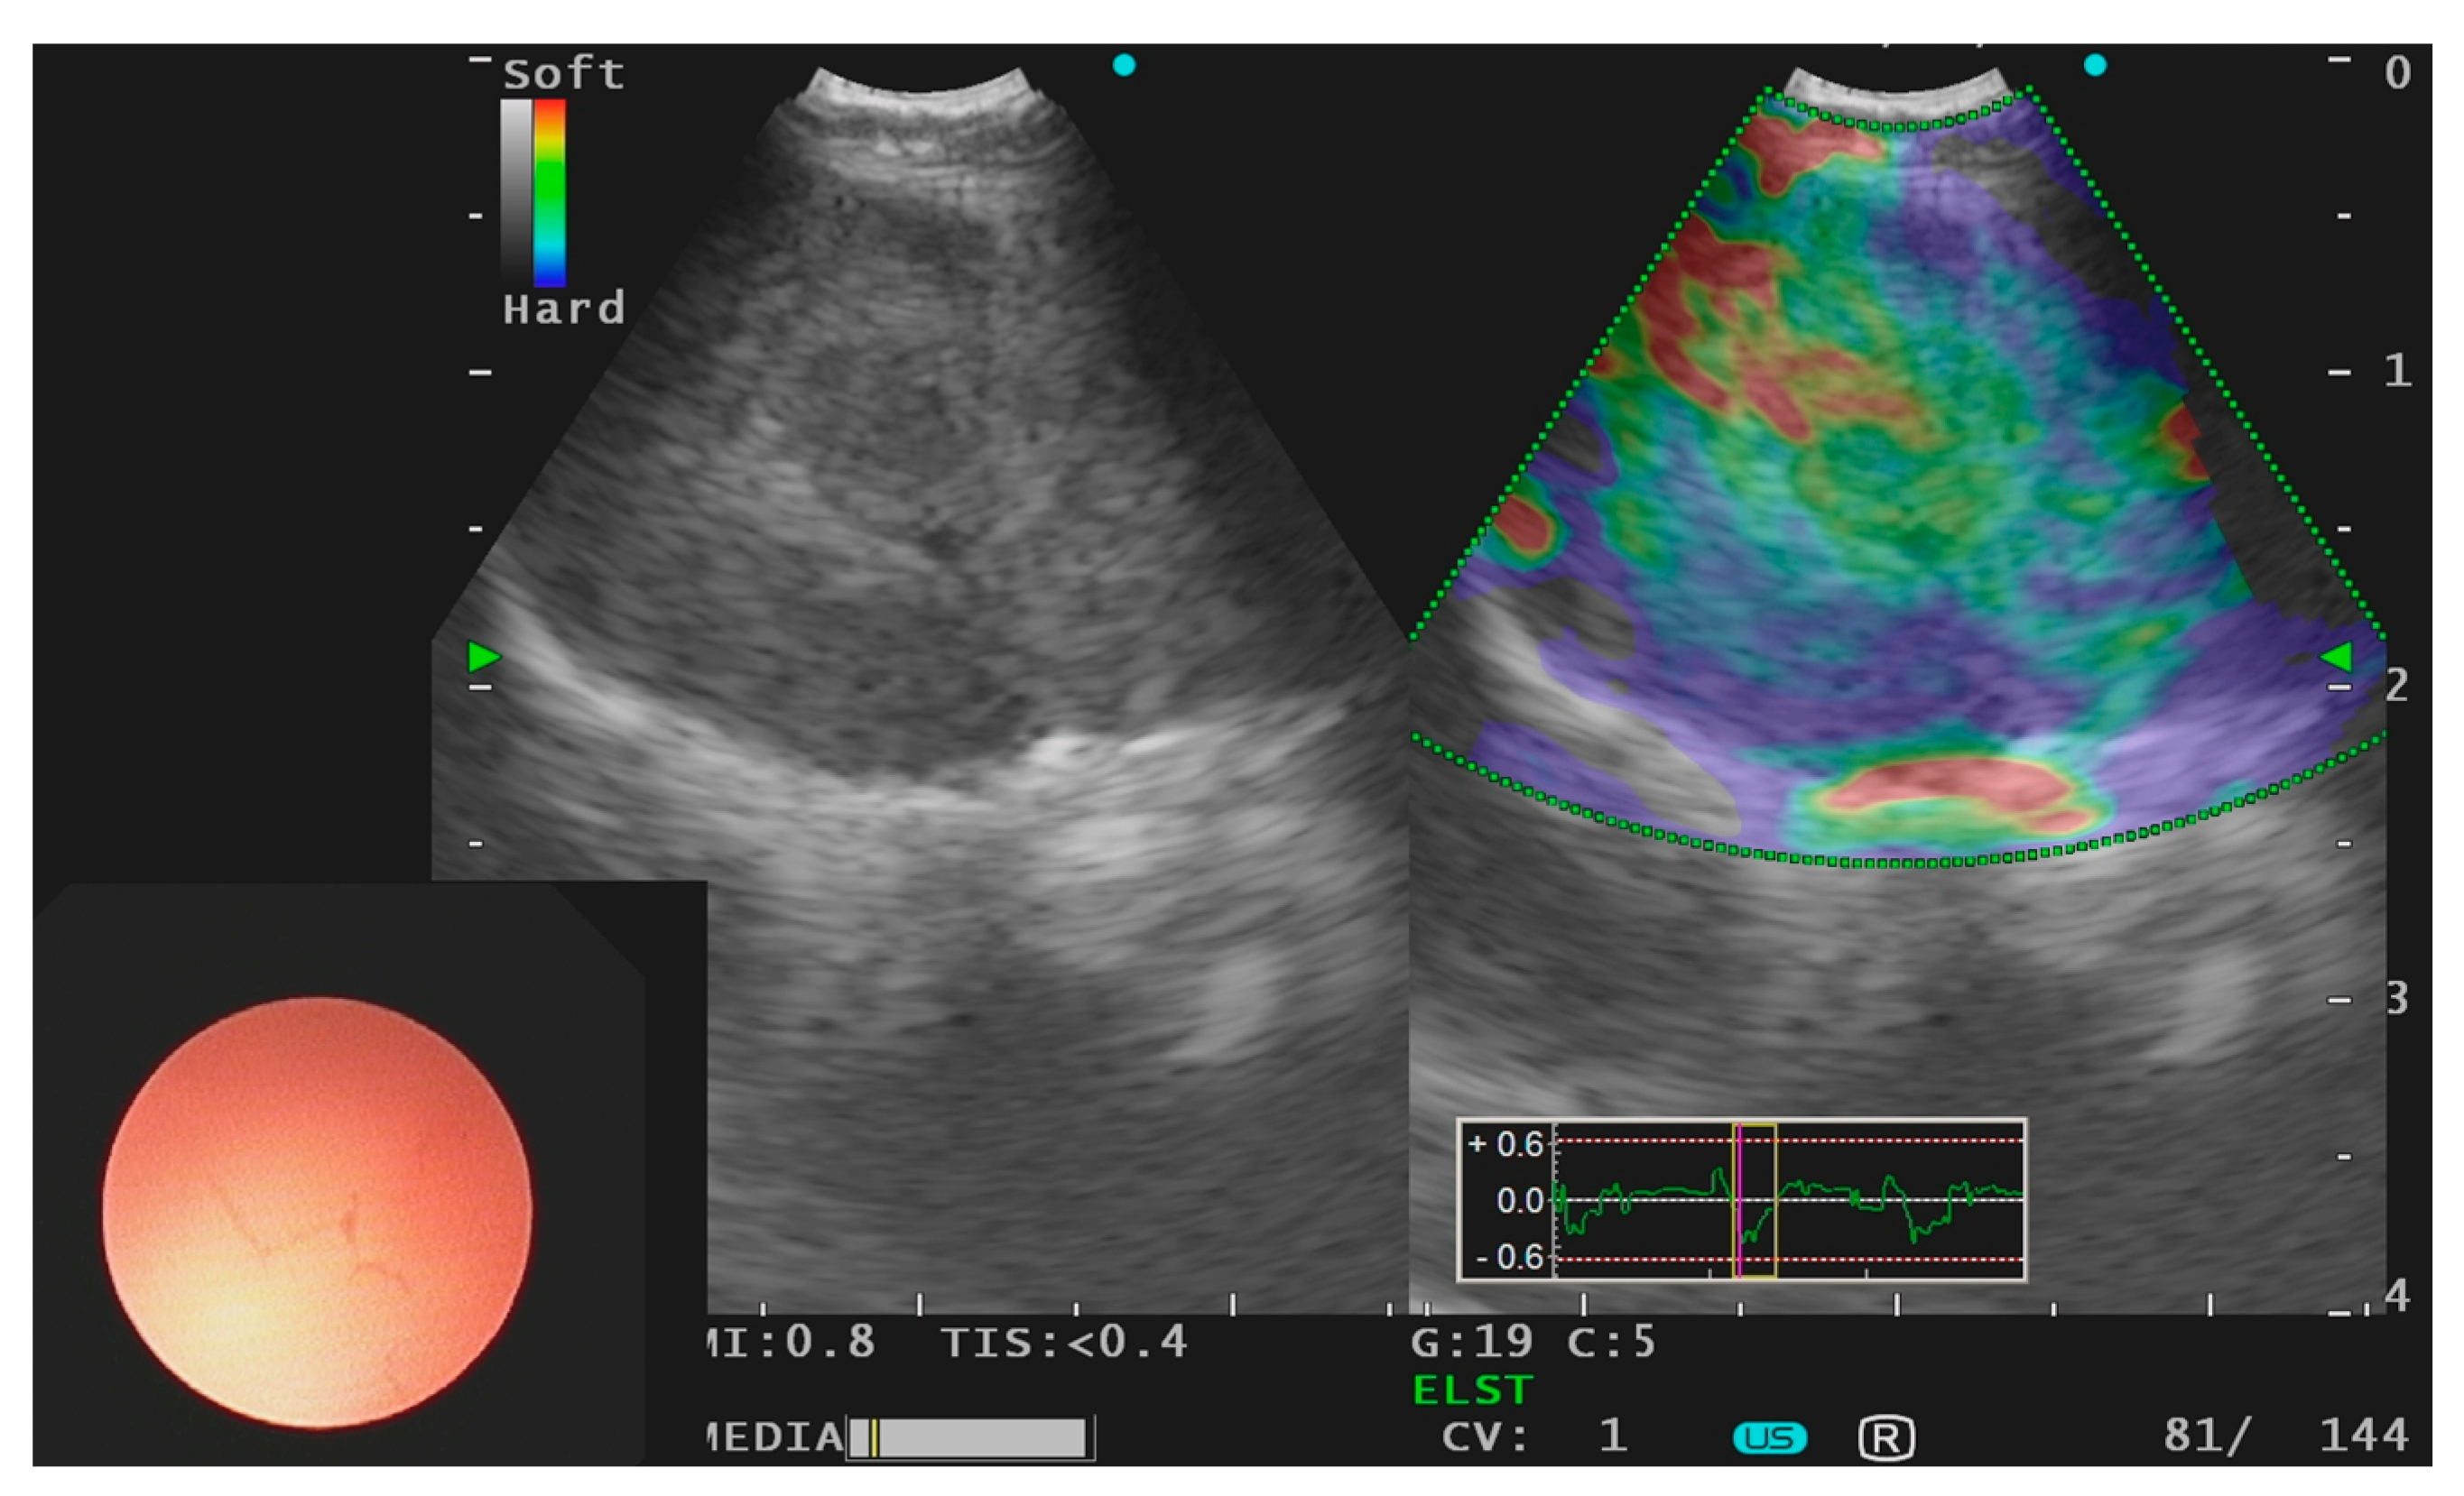

- Fujiwara, T.; Nakajima, T.; Inage, T.; Sata, Y.; Sakairi, Y.; Tamura, H.; Wada, H.; Suzuki, H.; Chiyo, M.; Yoshino, I. The combination of endobronchial elastography and sonographic findings during endobronchial ultrasound-guided transbronchial needle aspiration for predicting nodal metastasis. Thorac. Cancer 2019, 10, 2000–2005. [Google Scholar] [CrossRef] [Green Version]